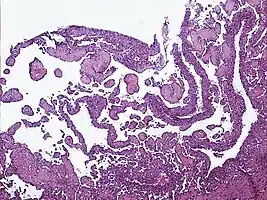

| Micrograph of a kaposiform hemangioendothelioma with "glomeruloid" nodules of endothelial cells. | |

- Kaposiform hemangioendothelioma (also known as "Infantile kaposiform hemangioendothelioma"[4]) is an uncommon vascular tumor, first described by Niedt, Greco, et al. (Hemangioma with Kaposi's sarcoma-like features: report of two cases.(Niedt GW, Greco MA, Wieczorek R, Blanc WA, Knowles DM 2nd. that affects infants and young children, with rare cases having also been reported in adults. Pediatr Pathol. 1989;9(5):567-75.)[3]: 596 [4]: 1782